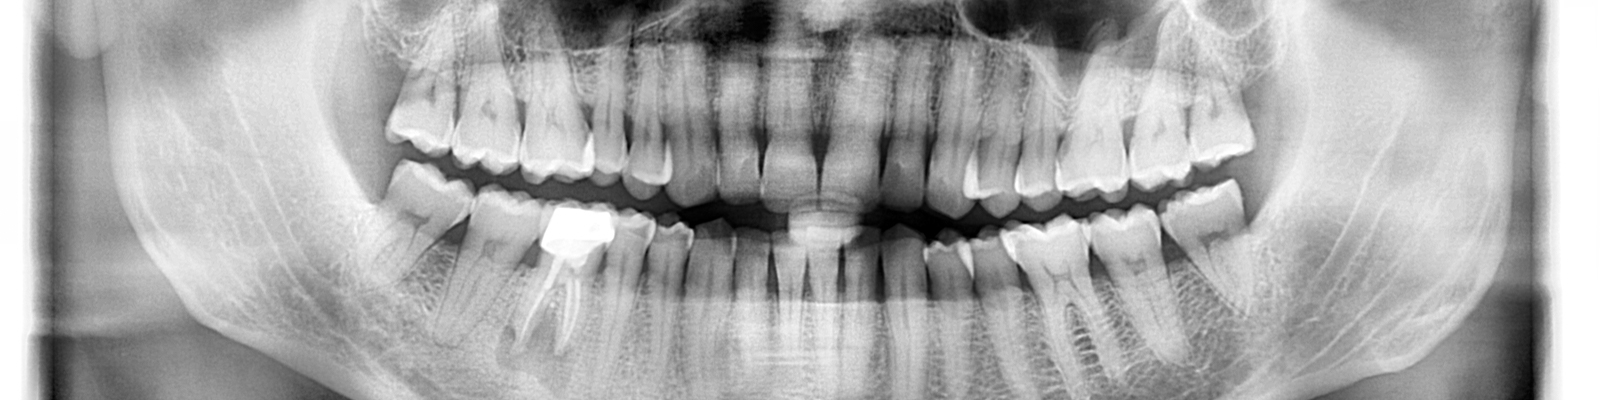

Panoramatické RTG s kefalo projekcí od výrobce Acteon (Satelec), jsou svými parametry a cenovou dostupností nejlepší volbou pro stomatologické praxe. Jedná se o OPG s kefalo ramenem, která svou kvalitou a ovládáním předčí všechna očekávání a řadí se tak mezi nejpoužívanější OPG v ortodontických ordinacích ve světě i u nás. Společnost Fénix Dental dodává všechny přístroje s odborným zaškolením a to dle individuální potřeby každého uživatele. Díky Aies SW je zobrazení OPG snímků bezkonkurenční. Díky panoramatickému RTG od výrobce Acteon, získáte nejpřesnější diagnostickou hodnotu, která snese ta nejpřísnější měřítka. Společnost Fénix Dental je autorizovaný servis pro produkty Acteon. Získejte precizní, přesné a kvalitní OPG snímky, kontaktujte nás.